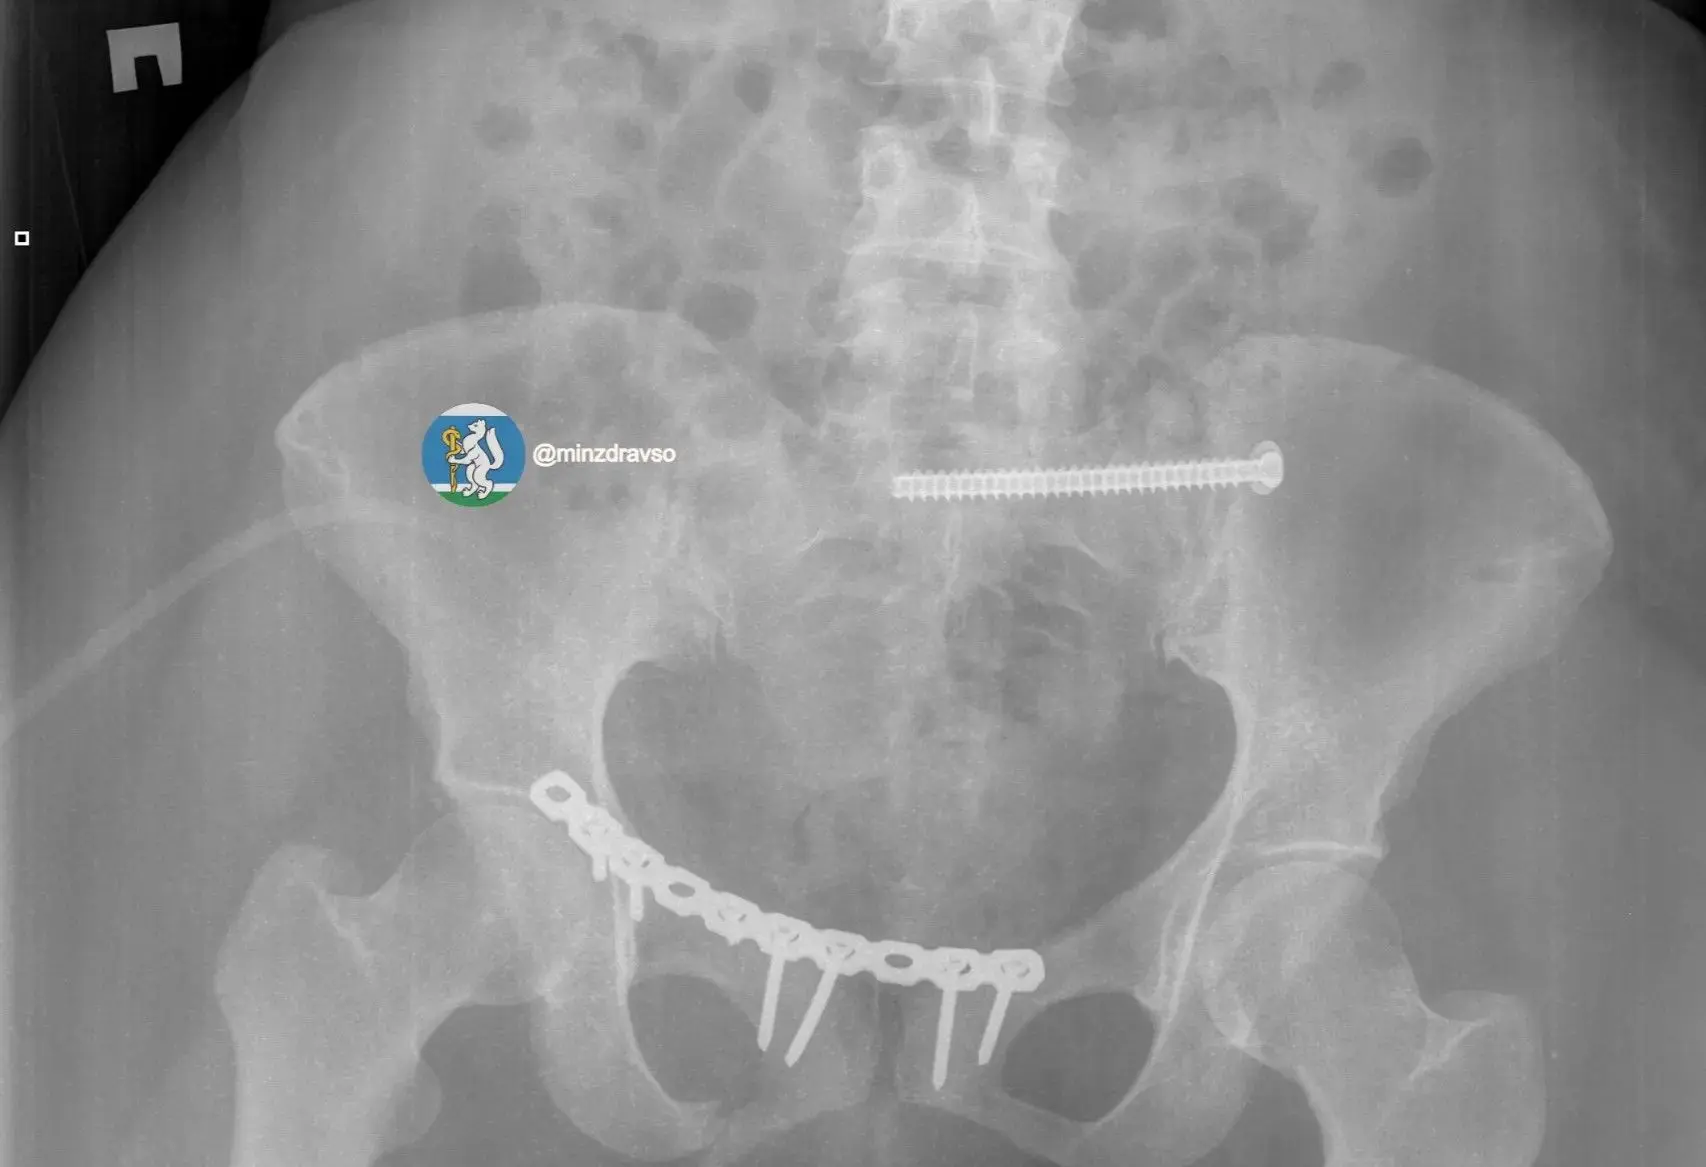

Крайне тяжелое повреждение таза представляло высокий риск массивной кровопотери, поэтому борьба за жизнь пациентки началась с немедленной стабилизации ее состояния. Медики качественгно скрепили отломки костей всех поврежденных сегментов костей и таза аппаратами внешней фиксации.